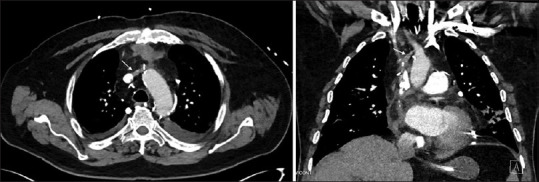

Misplacement of a Left Internal Jugular Central Venous Catheter in the Pericardiophrenic Vein.